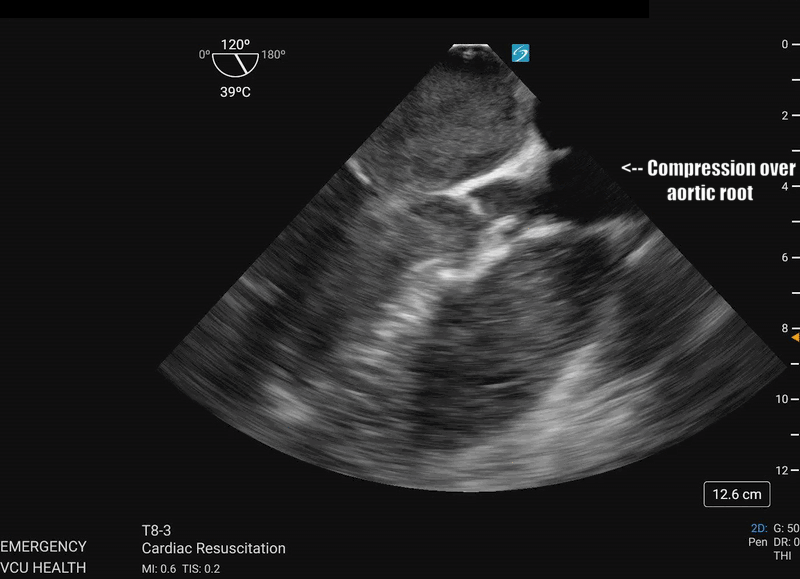

Most importantly for the resuscitationist, the ME-LAX view is used to evaluate the quality of CPR and hand placement for chest compressions; so it should be obtained during initiation of CPR and even when changing CPR providers if possible. Optimal chest compressions should result in vigorous LV squeeze with near concurrent aortic valve opening (Figure 2). Incorrect compressions, usually too high on the chest wall, will result in LV outflow obstruction and ineffective CPR (Figure 3). This can be seen on the ME-LAX view as squeeze over the AV itself, narrowing of the aortic outflow tract, absence of LV compression and/or absence of aortic valve opening during compressions. Signs of ineffective CPR should prompt adjustments in compression location and/or depth and subsequent re-evaluation for effectiveness.2

Figure 3: ME-LAX view during CPR (slowed to 50% speed) showing complete compression of the aortic root during CPR